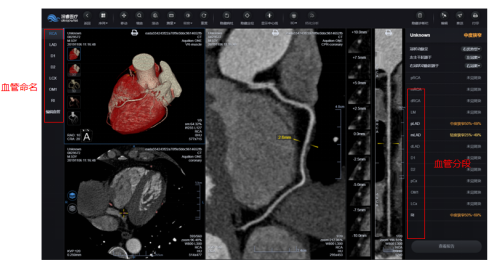

冠状动脉CTA-AI辅助诊断系统可以发挥大批量、快速处理图像数据的能力,提供影像重建和辅助诊断功能,节省医生时间,减轻工作量,降低误诊/漏诊率。目前应用于智能三维重建、斑块类别及狭窄程度的智能辅助诊断等。